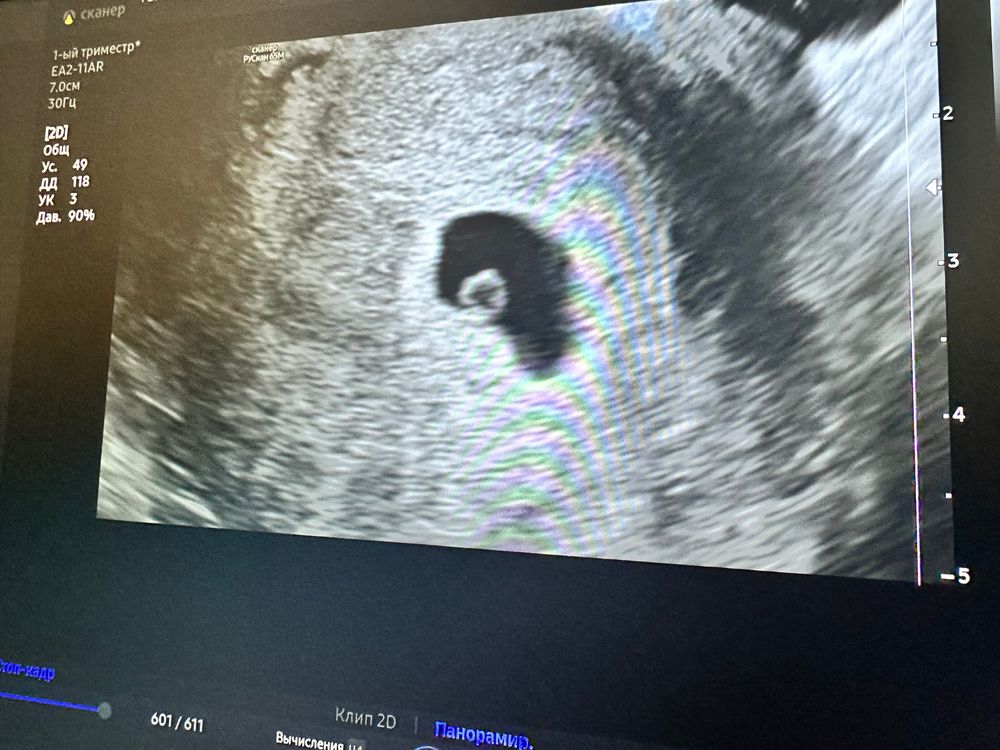

16 дз УЗИ фото приложу ,5недель 3 дня,плодное яйцо в матке, жм 0,3 мм, эмбрион чётко не видно, мои бежевые выделения это небольшая отслойка, назначили тронексам и дюфастон, начала пить, контрольное узи через дае недели.